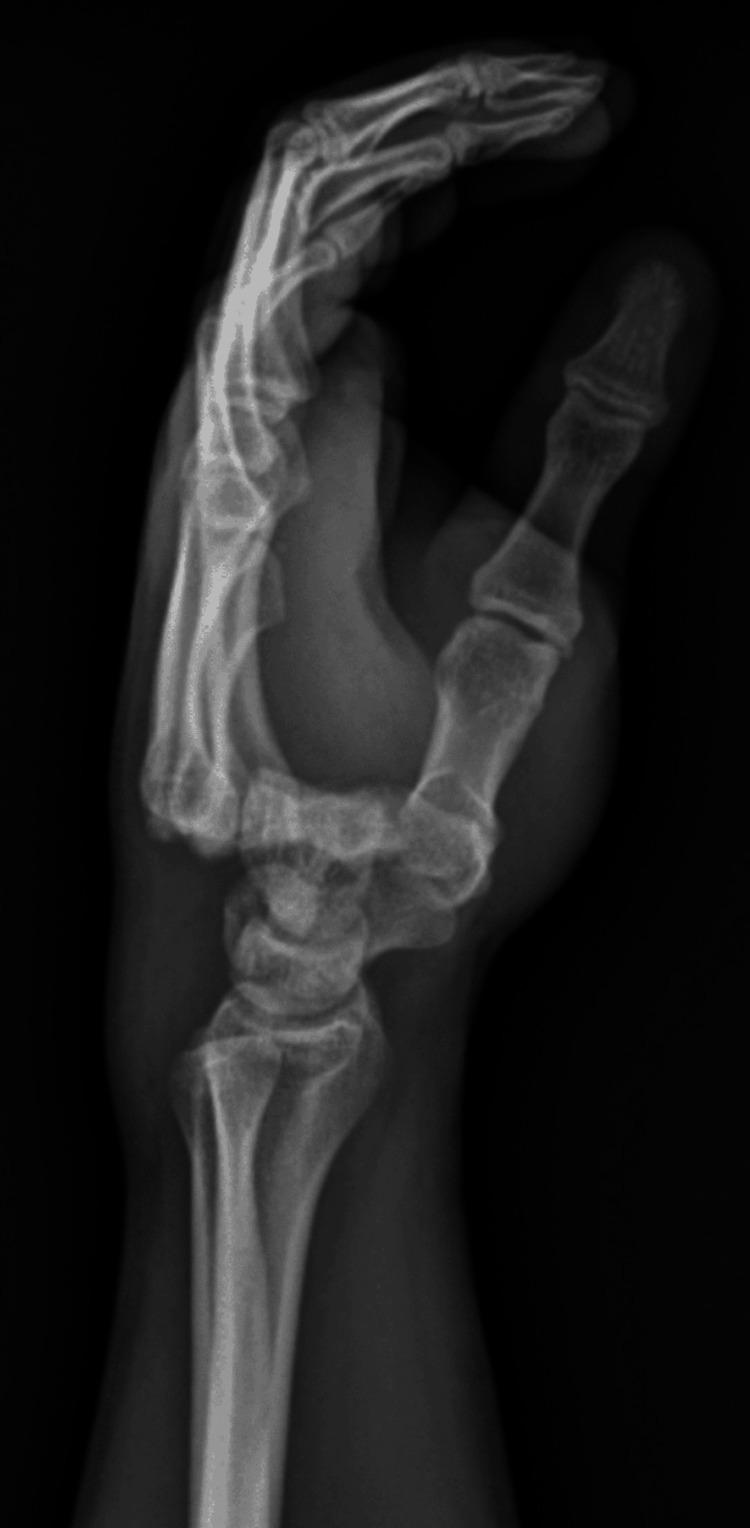

Carpometacarpal (CMC) joint fractures-dislocations are rare due to the complex structure of the carpal bones and strong ligamentous support; while the clinical image is usually "noisy," they present significant management challenges due to the unstable nature of the injury. These injuries are typically caused by high-energy trauma and frequently result in dorsal dislocations. Treatment requires a careful balance between the immobilization and surgical restoration of the anatomical alignment to prevent complications. This report highlights a case of four CMC joint dislocations managed conservatively, yielding positive outcomes despite the usual indications for surgical intervention, avoiding any possible anesthesiological or surgical complications.